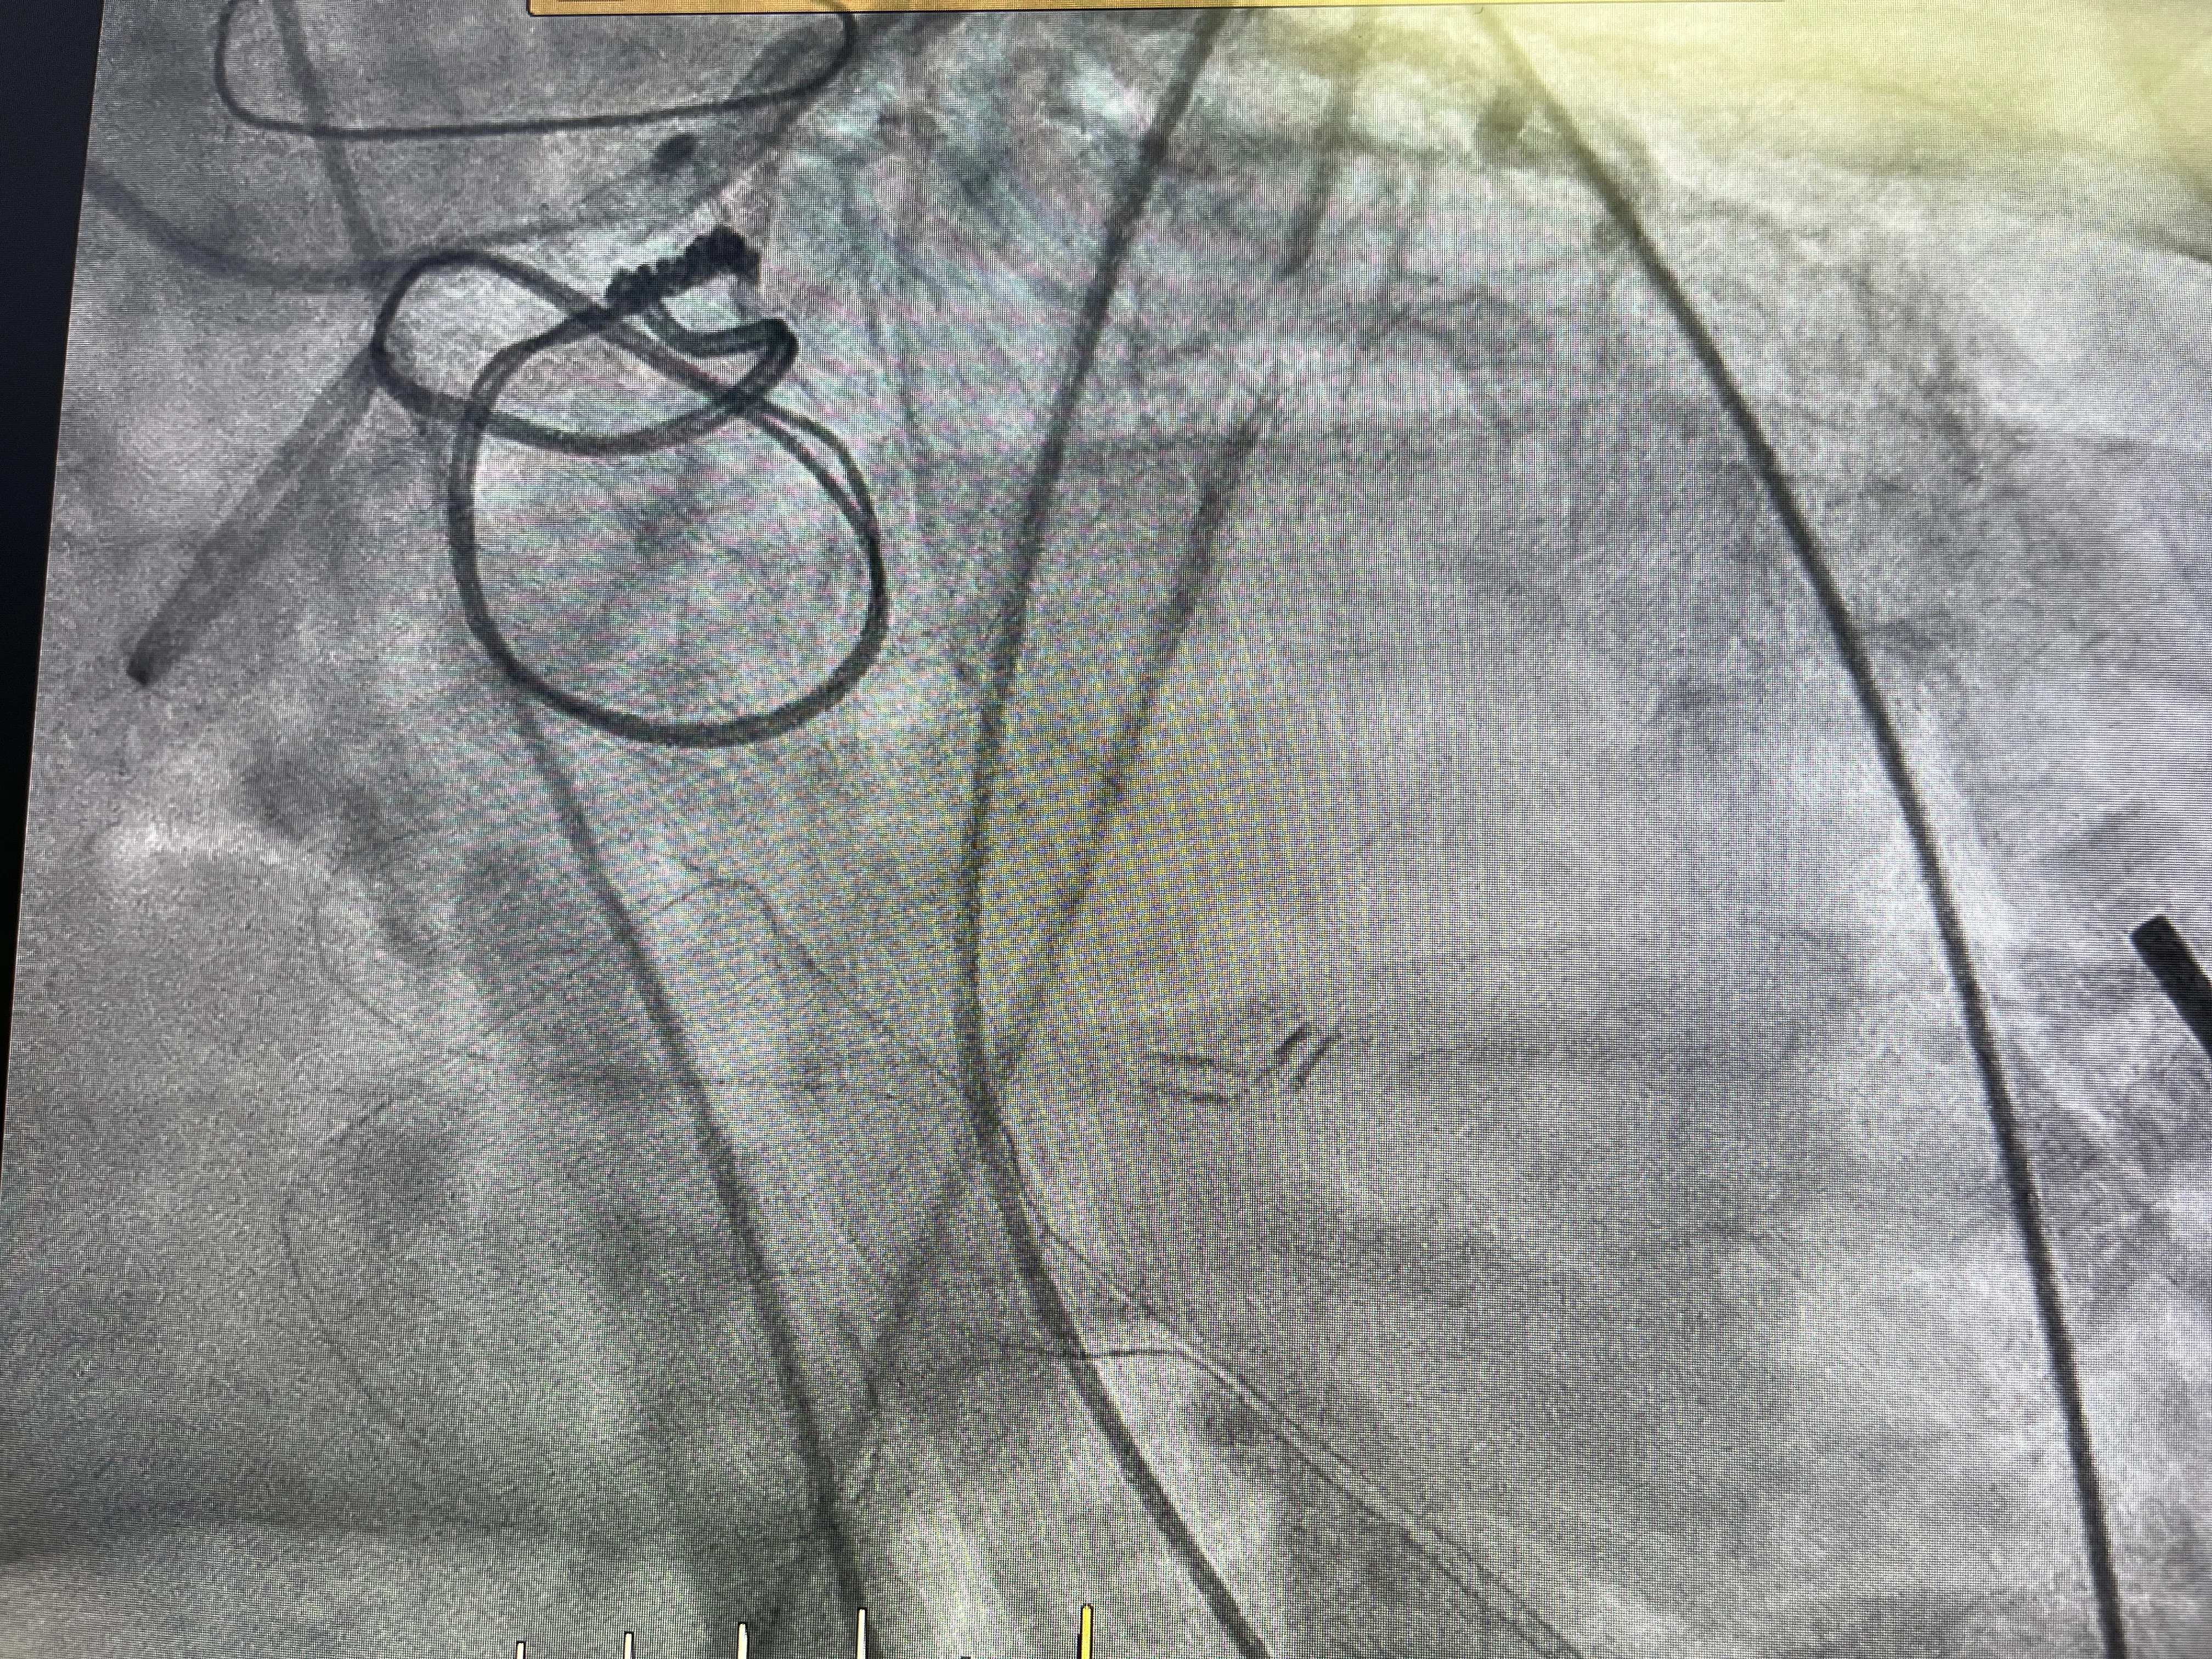

Cateterismo cardíaco izquierdo por vía radial: visión práctica

Una guía detallada sobre el procedimiento y sus beneficios en la cardiología moderna